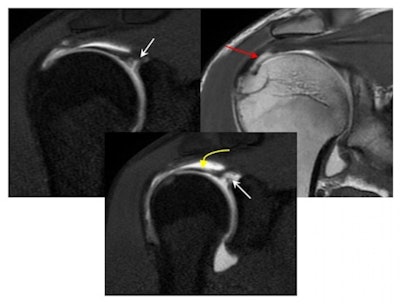

The acromioclavicular joint is subjected to repeated microtrauma and increased stress to the subchondral bone on the distal clavicular side, predisposing to subchondral fractures and distal clavicular osteolysis. Acromioclavicular joint cartilage damage and accelerated osteoarthritis might follow, they pointed out.

"Radiographs help to show more advanced stages with distal clavicular cortical erosions and joint space widening. The superiority of MRI is in demonstrating early and occult abnormalities before becoming evident on x-ray. Fluid-sensitive sequences show bone edema while T1-weighted imaging is better at showing cortical erosions and subchondral fractures."

Repeated arm lifting results in continuous friction and perhaps impingement of the rotator cuff tendons in the subacromial tunnel, the authors noted. Subacromial bursitis and various forms of supraspinatus tendinopathies and often tears are encountered as a result in weightlifters. Ultrasound and MRI are helpful in allowing accurate evaluation of the size and extent of these tears.